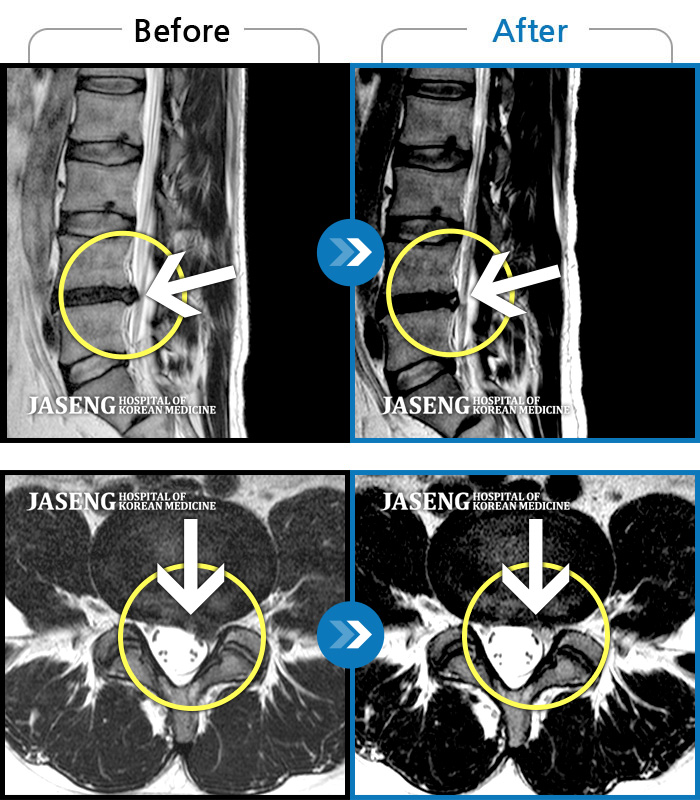

179 MRI ũ ʸ Ȯϼ.

[뱸] 19.11.28~25.05.06

ȯںп Ǹ ǿ ԿǾ, ο ġ ۿ Ƿ ġḦ Ͻñ ٶϴ.